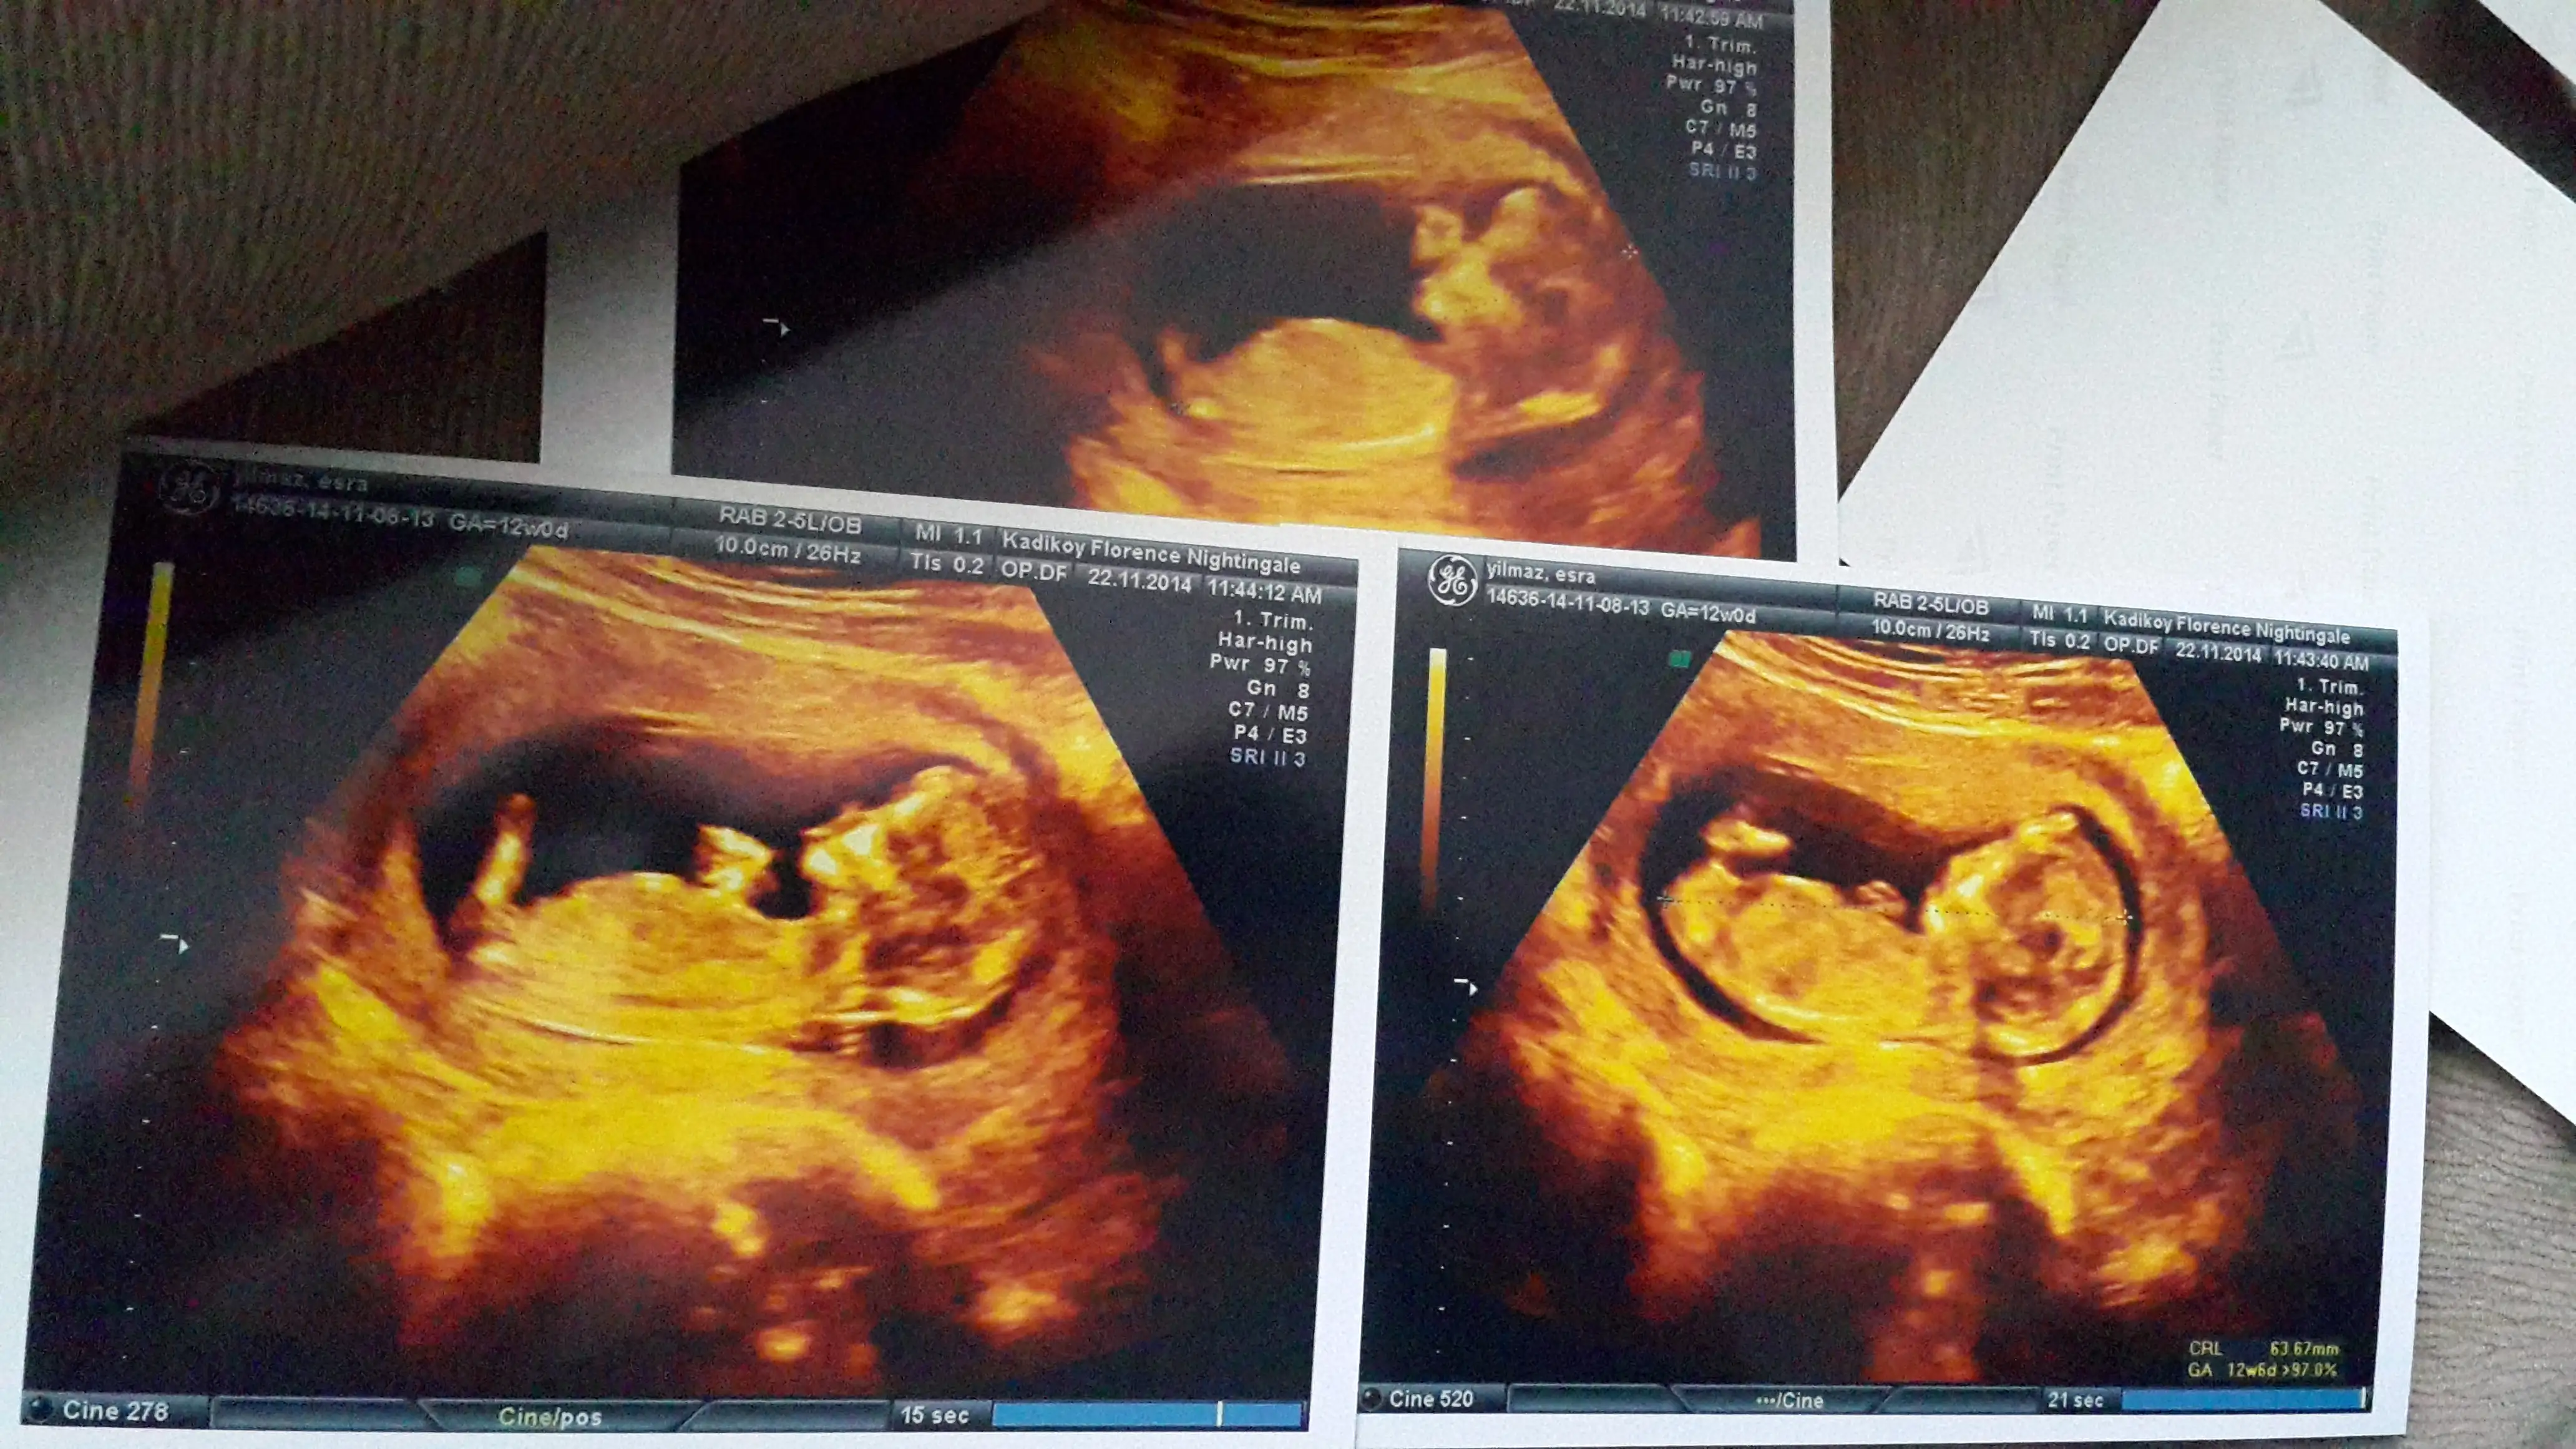

Canim resmini nub teorisi sayfasinda paylasayim bakalim ne dicekler orkidemde orda gorurse cvp verir haber ederimdenizkinub7 .!.:Canim esim bebisi videoya cekmisti ordan kopyaladigim bir resmi ekledim doktorun tam cikintisini isaretleyip gosterdigi yerin resmi. Onuda paylasmak istedim bi bakarsin tekrar doktorla ayni fikirdemisiniz merak ettim senin yorumunudaEki Görüntüle 1311947 Eki Görüntüle 1311948 Eki Görüntüle 1311949